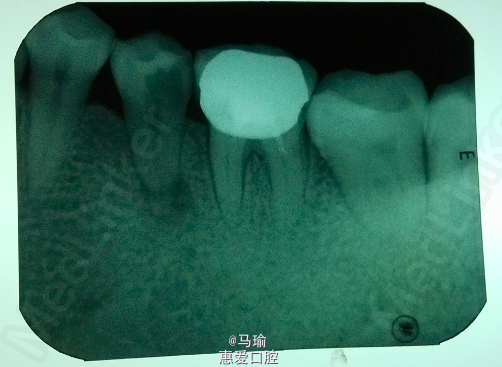

检查:35牙远中邻合面龋坏,龋坏较深,已穿髓,探(-),冷(-),叩(++),I度松动,唇颊侧未见明显瘘道。 x线片示35牙远中邻合面牙体组织密度减低影,与髓腔相通,根尖周组织暗影,根尖1/4处疑似根折,远中暗影。

诊断:1、35牙慢性根尖周炎 2、35牙根折? 治疗计划: 1、35牙根管治疗+树脂充填+冠修复 2、35牙拔除 处置:治疗前告知患者35牙可能存在根折,需要根尖外科手术或拔除等其他治疗,患者知情同意。 常规根管扩挫,根测仪可测得根管长度,试尖可,封药后预约复诊。 患者复诊时无不适,遂行根管充填,拍片后意外发现疑似根折的地方有糊剂溢出,磷酸锌暂封,嘱患者3月后复诊。

3月后患者复诊,x线片示根尖周暗影减少,患者无不适,遂行树脂充填,嘱患者修复科冠修复。 讨论:这种侧支根管的暗影特别像根折,会影响医生的判断,且与根尖周炎的症状有相同之处,因此不太能区分,只有在做的过程中去判断,不过事先得向患者说明情况。不知大家有没有遇到过这种情况?